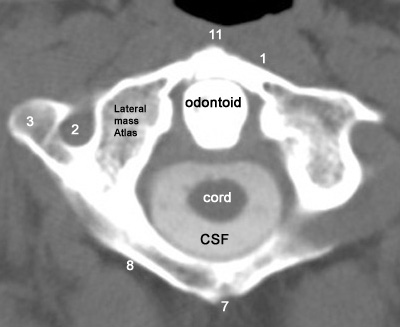

1: Anterior arch  2: Transverse foramen  3: Transverse process  7: Rudimentory spinous process

8: Posterior arch  11: Tubercle